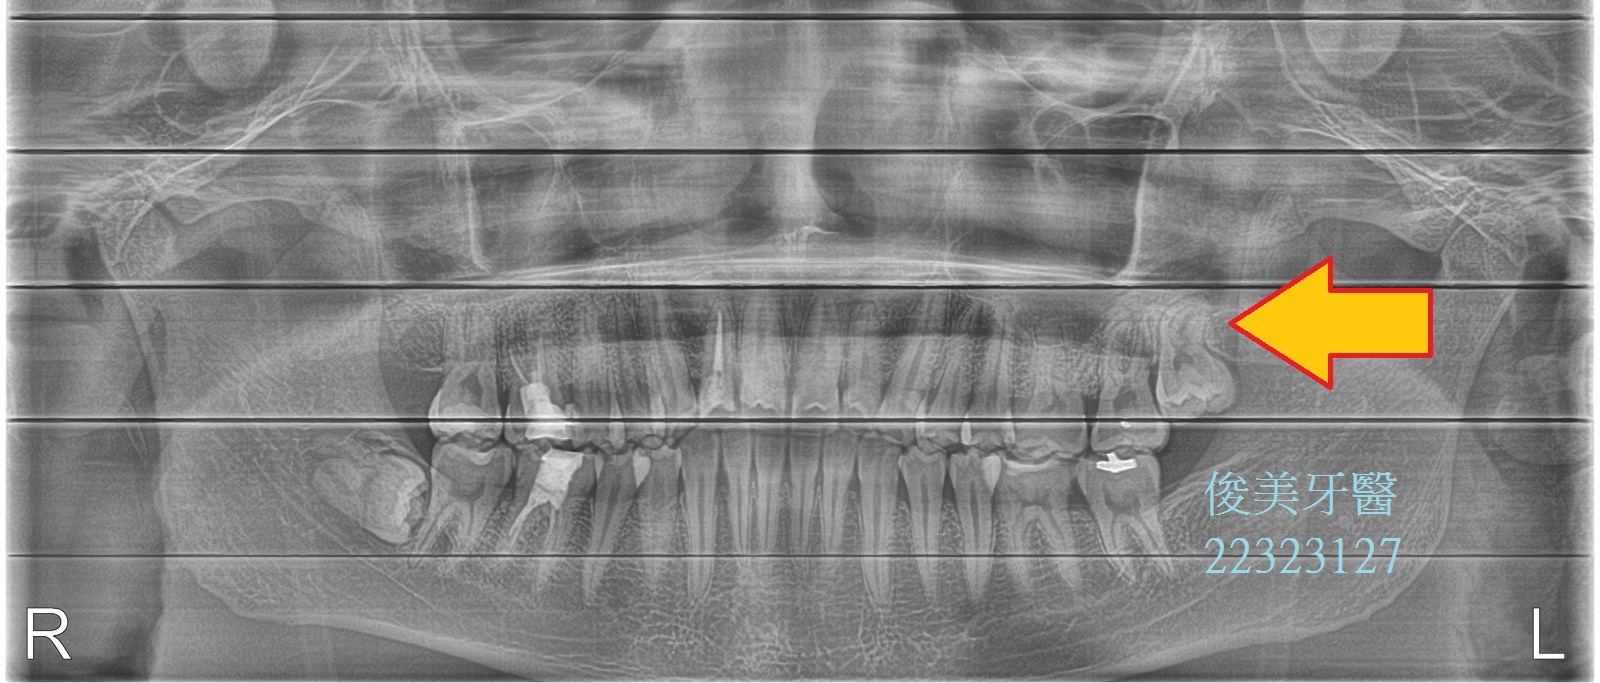

埋伏智齒拔牙案例9

患者於門診中表示,牙齒不舒服,且牙齒有排列的問題;經醫師檢查後,發現患者有兩顆埋伏的智齒未拔除,會推擠其他牙齒,造成牙縫易塞,

不易清潔且牙齒受力不平均。

建議先拔除源頭,就是智齒的干擾。

牙齒已無多餘的空間可生長,造成牙根彎曲。

雖智齒本身沒有蛀牙,但造成的咬合干擾却無法回復。